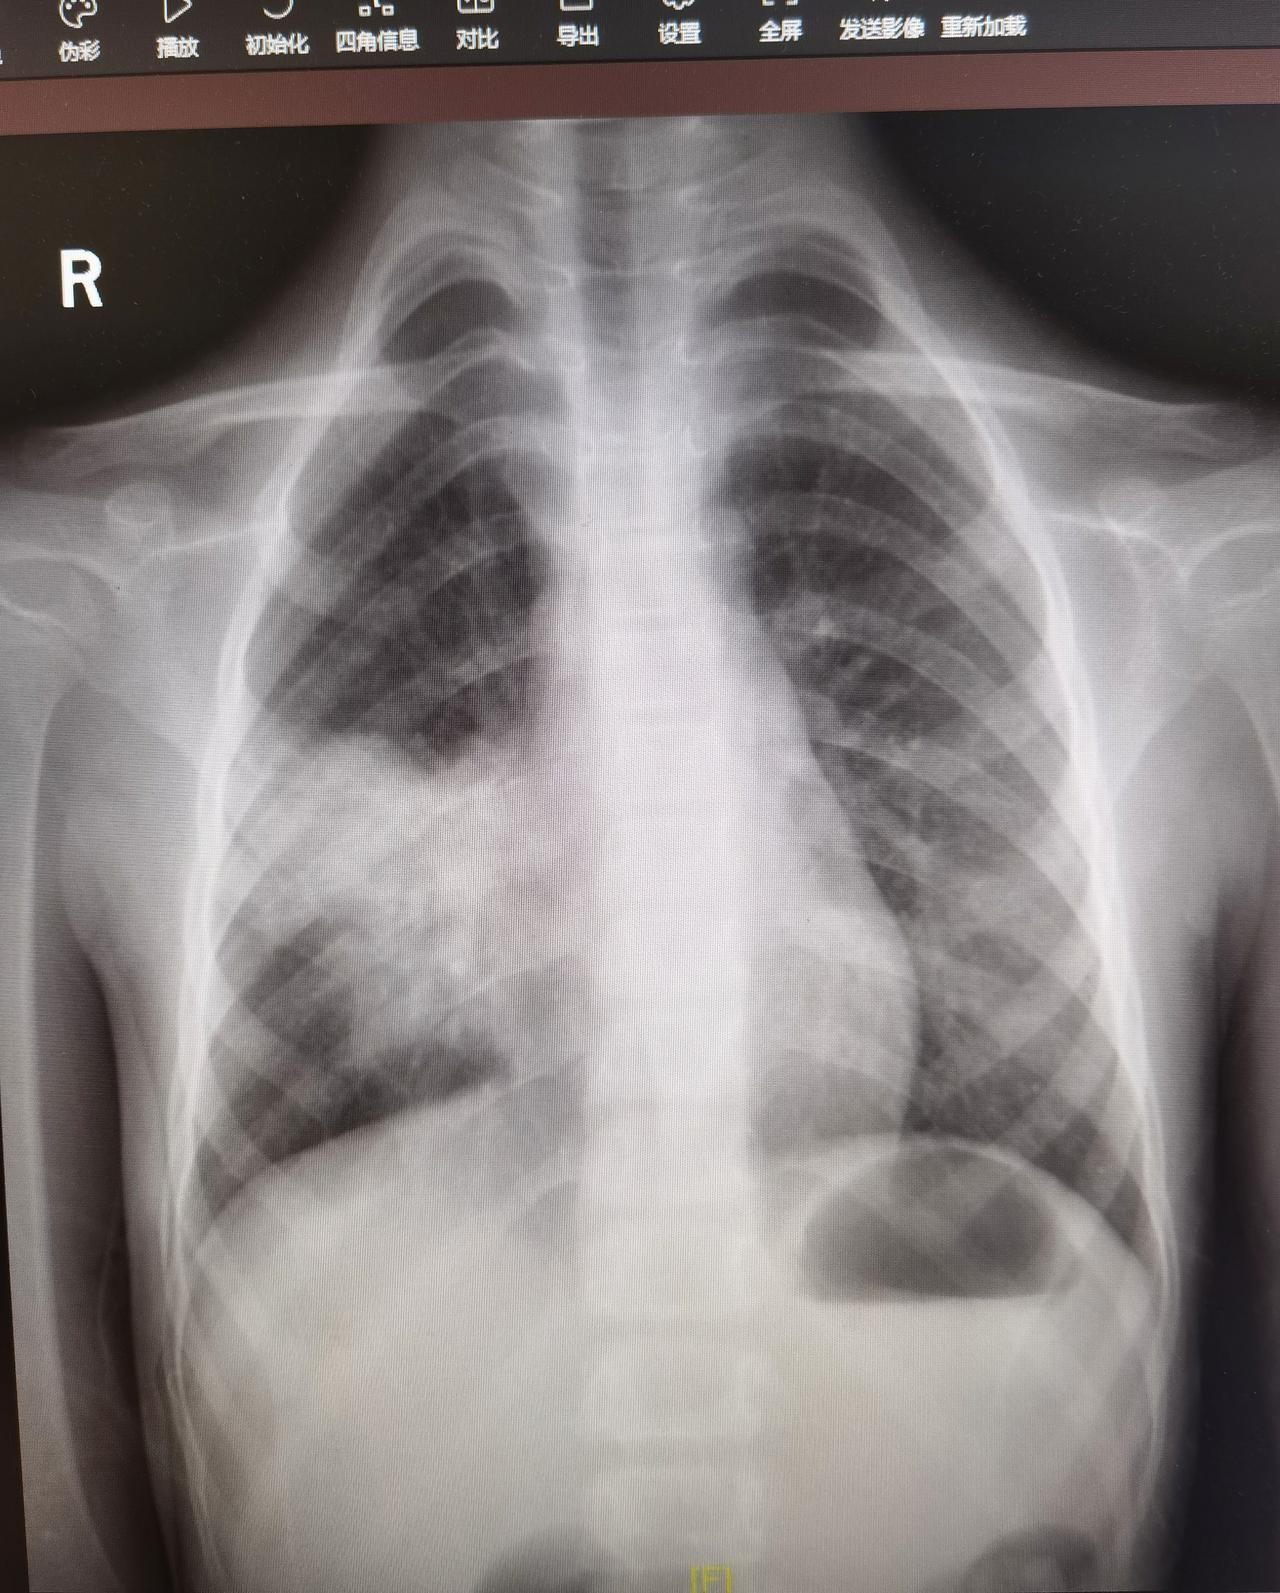

12岁女孩,初中生,间断发热七天。病初高热就确诊流感,吃了奥司他韦有改善,但还没完全退烧家长就让孩子上学去了,药物也是时用时不用。 期间退烧两天,后咳嗽突然加重并再次高热,一边上学一边吃退烧药扛,第三天就受不住了,来就诊,结果肺炎。合并肺炎支原体感染。 只能住院了。 关于流感退烧后再次发热,考虑以下几种情况。 1.用药疗程不足。奥司他韦抗病毒的机制是抑制病毒复制,常规疗程五天,提前停药可能会导致病毒在体内再次复制,所以疾病反复,出现发热。 2.出现其他并发感染。在疾病期和恢复期,机体免疫力相对较低,如果接触了其他病原体,极易合并感染。在学校,环境相对密闭,人群密集、防护欠缺,病毒种类仅次于医院,很难避免感染。 3.流感并发症。少部分人流感后会出现一系列的并发症,如气管炎、肺炎、心肌炎、脑炎等等。一旦出现,可能会再次发热,同时伴随其他相应的临床症状。 4.甲流急性期的反复高热,导致体温调节中枢功能紊乱,出现了短时间的低热。这种情况一般不会伴随其他不适,宝宝一般情况好,精神胃纳也不错,大多不需特殊处理,会自行恢复。 近期,各类病原体流行,感染后的并发症、后遗症等等问题频发,各位家长需高度警惕。